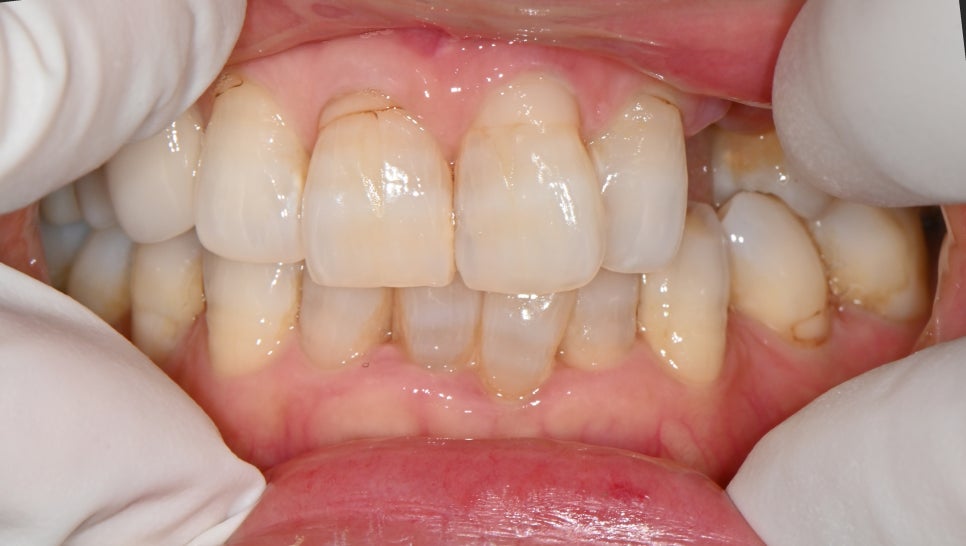

👀 Appearance at the time of visit

📸 Initial consultation photo

Initial front-view photo of the osteomyelitis patient